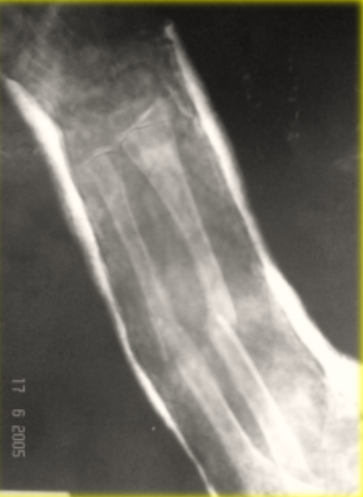

En un paciente con una fractura con esta radiografia, que tratamiento se recomienda?

Clavillos + yeso, fijador externo o placas